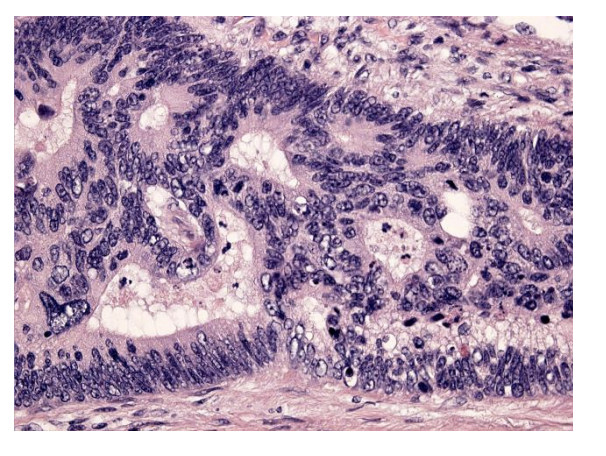

57-årig mand henvist fra e.l. til gastroskopisk udredning grundet længerevarende anamnese med daglige refluxsymptomer (halsbrand, sure opstød og sviende smerter i epigastriet). Ved gastroskopi ses i distale esophagus uregelmæssige røde tunger der strækker sig op i esophagus. Der biopteres herfra og mikroskopisk ses forandringer, som på billedet. Hvilke epitelforandringer ses i biopsien?

a. Metaplastisk cylinderepitel af intestinal type

*a. Metaplastisk cylinderepitel af intestinal type

Det normale pladeepithel i oesophagus er erstattet af cylinderepithel: Barrets oesophagus